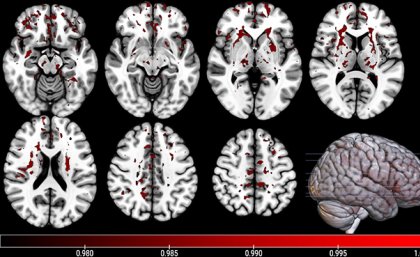

COVID-19 may have an impact on people’s cognitive and memory abilities that lasts a year or more after infection. A new study by Imperial College London researchers reveals small deficits in the performance of cognitive and memory tasks in people who had recovered from COVID-19 compared with those who had not had COVID-19. This includes […]